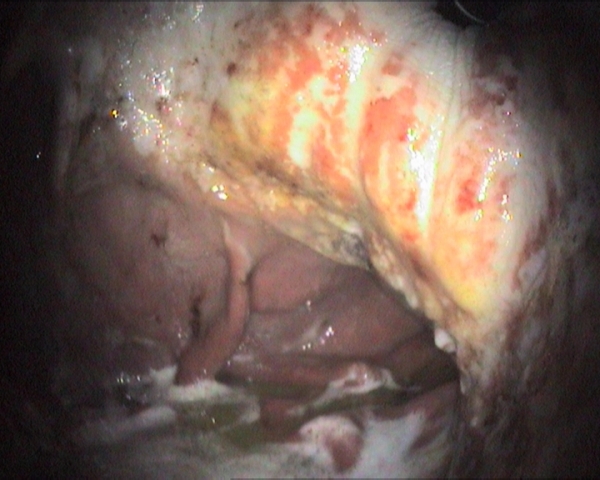

Equine Gastric Ulcer Syndrome (EGUS) is a serious and common condition and any type of horse can be at risk.1 EGUS can have a profound impact on a horse’s condition and performance and can be life threatening in foals. It is a challenging condition to diagnose as the clinical signs are often vague and not always present.1 Gastroscopy is the only method currently available for a definitive diagnosis. Of the two types of disease equine squamous gastric disease is graded on a numeric scale with 1 being the least severe and 4 being the most serious. Equine glandular gastric disease can be very varied in terms of location and type so grading this disease on a score system is no longer recommended. Instead it is now usually described in terms of location, severity and appearance.2

The new interactive tool helps vets to illustrate and record gastroscopy findings. This information, together with treatment and management recommendations, can be shared easily with the client. Posters explaining gastric ulceration have been designed to help increase awareness and understanding of EGUS amongst horse owners.